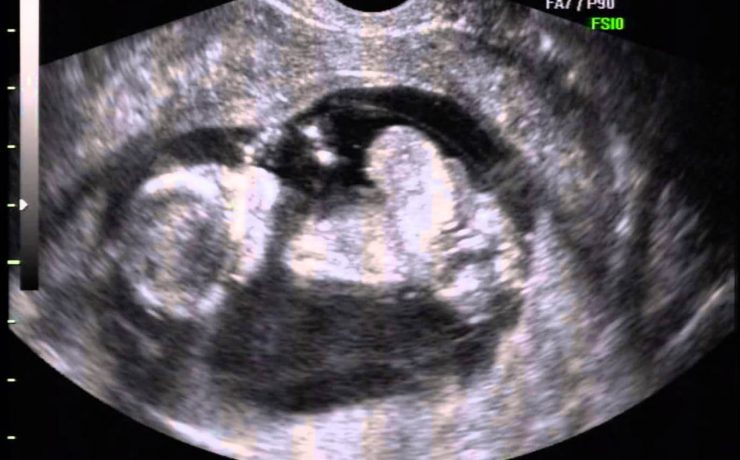

El síndrome de Rokitansky, es la anomalía más grave del tracto reproductivo femenino. Consiste en la ausencia congénita de vagina y útero ausente o rudimentario, como consecuencia de la falla en el desarrollo Mûlleriano de la vagina y el útero. Este síndrome fue descrito por Rokitansky en 1838. Es la